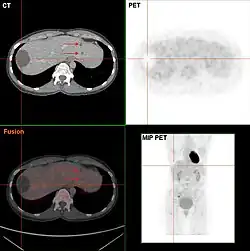

Zum interindividuellen Vergleich wird die Aktivität entweder auf das Körpergewicht (body weight, BW [g]), auf die fettfreie Körpermasse (lean body mass, LBM [kg]) oder auf die Körperoberfläche (body surface area, BSA [m²]) normiert. Bei Gleichverteilung der Radioaktivität ergibt sich ein SUV-Wert von 1, Werte größer eins beschreiben eine Anreicherung, Werte kleiner eins eine Abreicherung. Da ein Tracer im Körper nicht gleichverteilt wird, liegen in gesundem Gewebe meist Werte zwischen 1 und 2 vor – sofern dort keine physiologische Anreicherung stattfindet wie z. B. in Gehirn, Herz, Niere und Blase oder kaum FDG vorzufinden ist wie beispielsweise in Fettgewebe oder in Zysten (siehe Abbildung). Der SUV-Wert ist eine Hilfe bei der Unterscheidung zwischen bösartigem (malignem) und gutartigem (benignem) Gewebe; in Tumoren kommen Werte bis ca. 20 vor, er unterliegt jedoch einer Reihe von Einflussfaktoren: